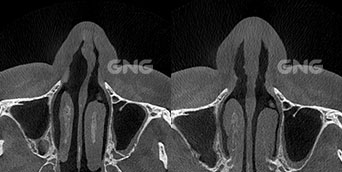

왼쪽 코의 코막힘 증상으로내원해주신 분입니다.코막힘 원인을 파악하기 위해 3D-CT를 촬영했는데요.아래 사진들을 보시면 비중격 만곡증 증상인휘어진 비중격의 모습을 육안으로 확인할 수 있습니다. 왼쪽에 뼈가 많이 튀어나와있고수술 후 해당 위치의 뼈가 제거되면서양쪽 비강, 특히 좁았던 왼쪽 부분이열린 모습을 볼 수 있습니다. <코막힘 원인> 수술 전, . . .